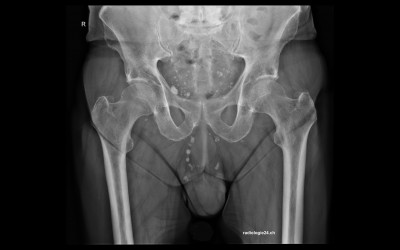

Röntgenfall des Monats August 2017 mit Auflösung

75 jähriger Patient therapierefraktäre Becken-/Hüftschmerzen rechts Diagnose/weitere radiologische Diagnostik?

Bild vergrössern